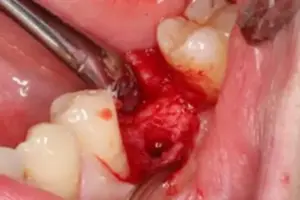

Am Ende des Eingriffs wird von mir direkt und vor Ort nochmal mittels Röntgenaufnahme die korrekte Position des Implantats überprüft. Dadurch stelle ich auf einem zusätzlichen Weg für Sie abschließend sicher, dass ich Ihren Implantat-Körper perfekt in den Knochen eingesetzt habe.

Bild 4: Röntgenkontrolle der Implantatsposition nach erfolgtem Eingriff

Nach der Röntgenbildaufnahme geht es zurück in eines meiner Behandlungszimmer. Herr F. bekommt das Röntgenbild gezeigt und erläutert, sodass er sich selbst davon überzeugen kann, dass der Implantat-Körper einwandfrei in seinen Kieferknochen eingesetzt wurde. Siehe Bild 4. Das Zahnfleisch wird nun über den frisch eingesetzten Implantat-Körper gelegt und vernäht. Siehe Bild 5.